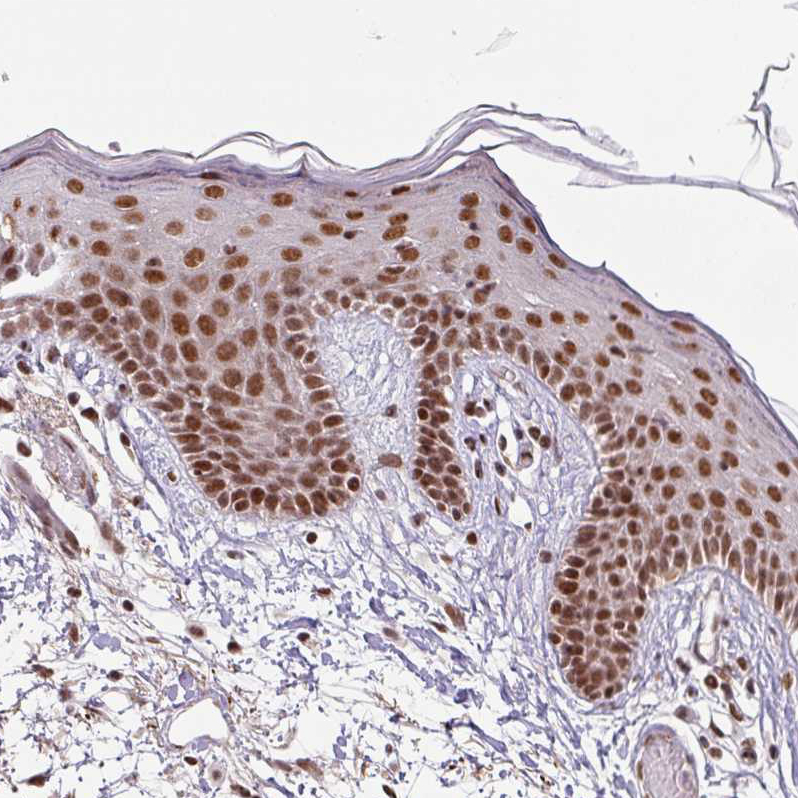

Immunohistochemical staining of human tonsil shows moderate to strong nuclear positivity in germinal center cells.